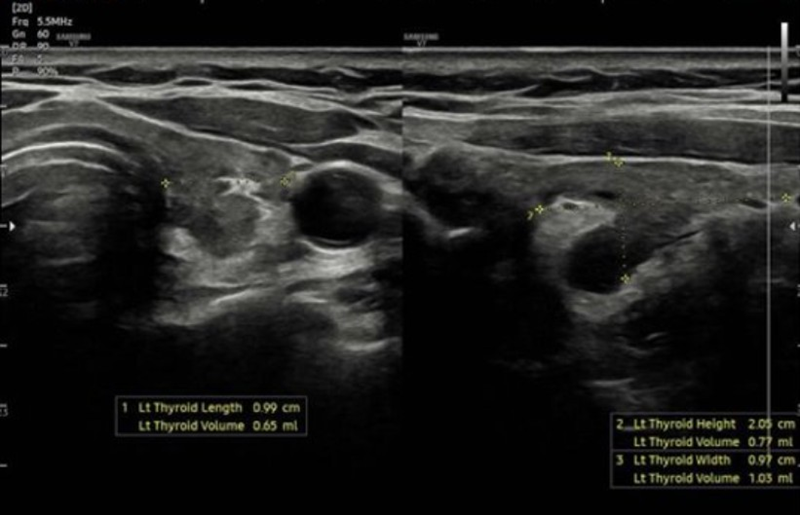

- Siêu âm tuyến giáp: Hình ảnh bệnh lý chủ mô tuyến giáp lan tỏa.

Siêu âm tuyến giáp gợi ý hình ảnh theo dõi bệnh lý chủ mô tuyến giáp lan tỏa